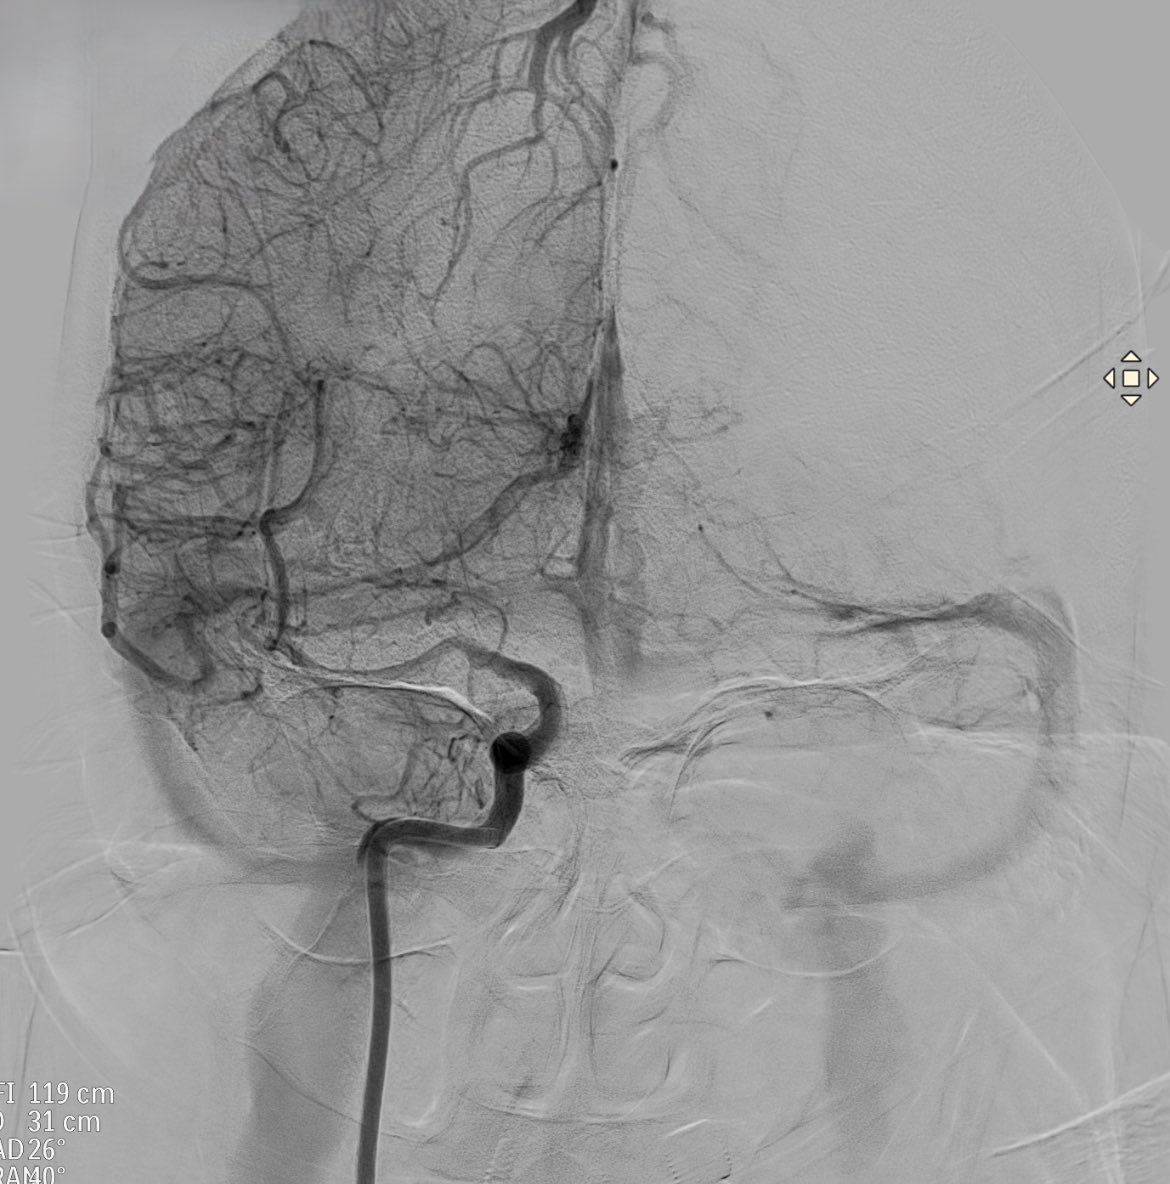

Patient admitted for ischemic stroke.

This is the arteriography prior to mechanical thrombectomy

Which artery is occluded ?

What anatomical variant is suspected ?

#Stroke

#Thrombectomy

#Neuroanatomy

#Anatomicalvariants

#Neurotwitter